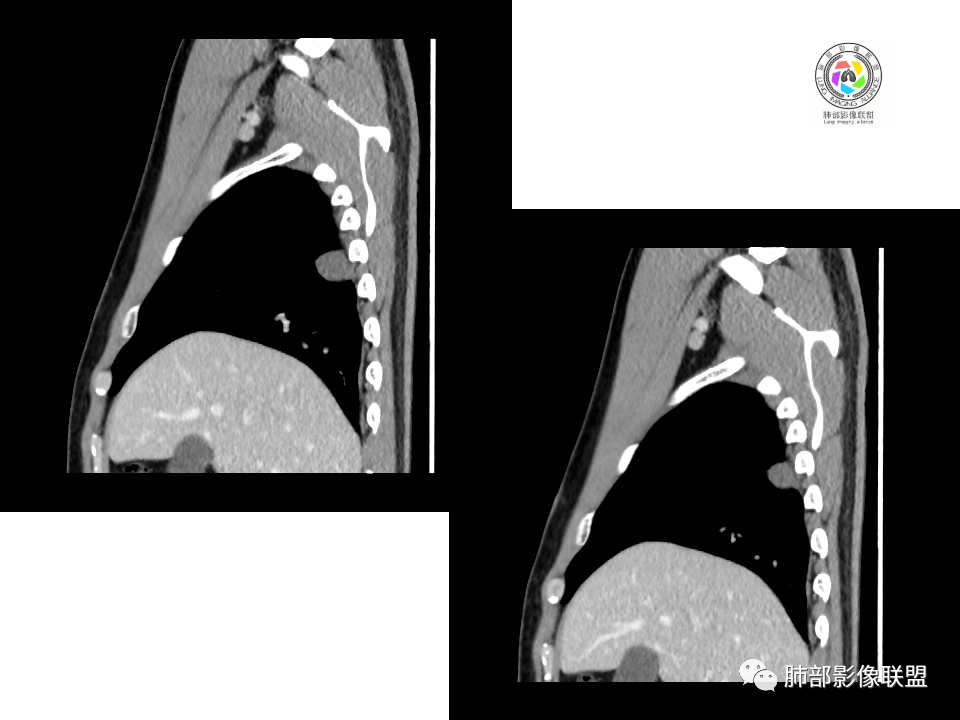

2.右肺下叶背段胸膜下块影,边界清楚光整,上下极见磨玻璃晕,未见明显分叶毛刺和棘状突起,未见胸膜凹陷或胸壁侵入。密度均匀,轻度不均匀强化。未见支气管进入。

显然本例焦点在于背段那个边缘光整的块影!

4.良性占位绕不过去,如发生于该部位的孤立性纤维瘤等……

病灶不均匀强化可以将含液支气管囊肿排除在外。

有老师分析,多发病灶有磨玻璃晕,可以符合隐球菌感染,确实如此。但背段边缘如此锐利的块影还是更容易让人联想到新生物。

5、周围毛刺纤维、边缘形态等:坏死包裹会使得结节变圆;结节多缺乏明显的分叶征,缺乏局部突出生长能力;如果出现分叶,是由多处肉芽肿中心形成。没有坏死的局限化,结节只是凑合在一起,常呈方形征;毛刺进入晕区(概念源自南边老师),毛刺较短、较软;周围的晕吸收后,会留下不规则边,外面常残留丝状条索;收缩力较弱,临近胸膜对胸膜牵拉不明显。